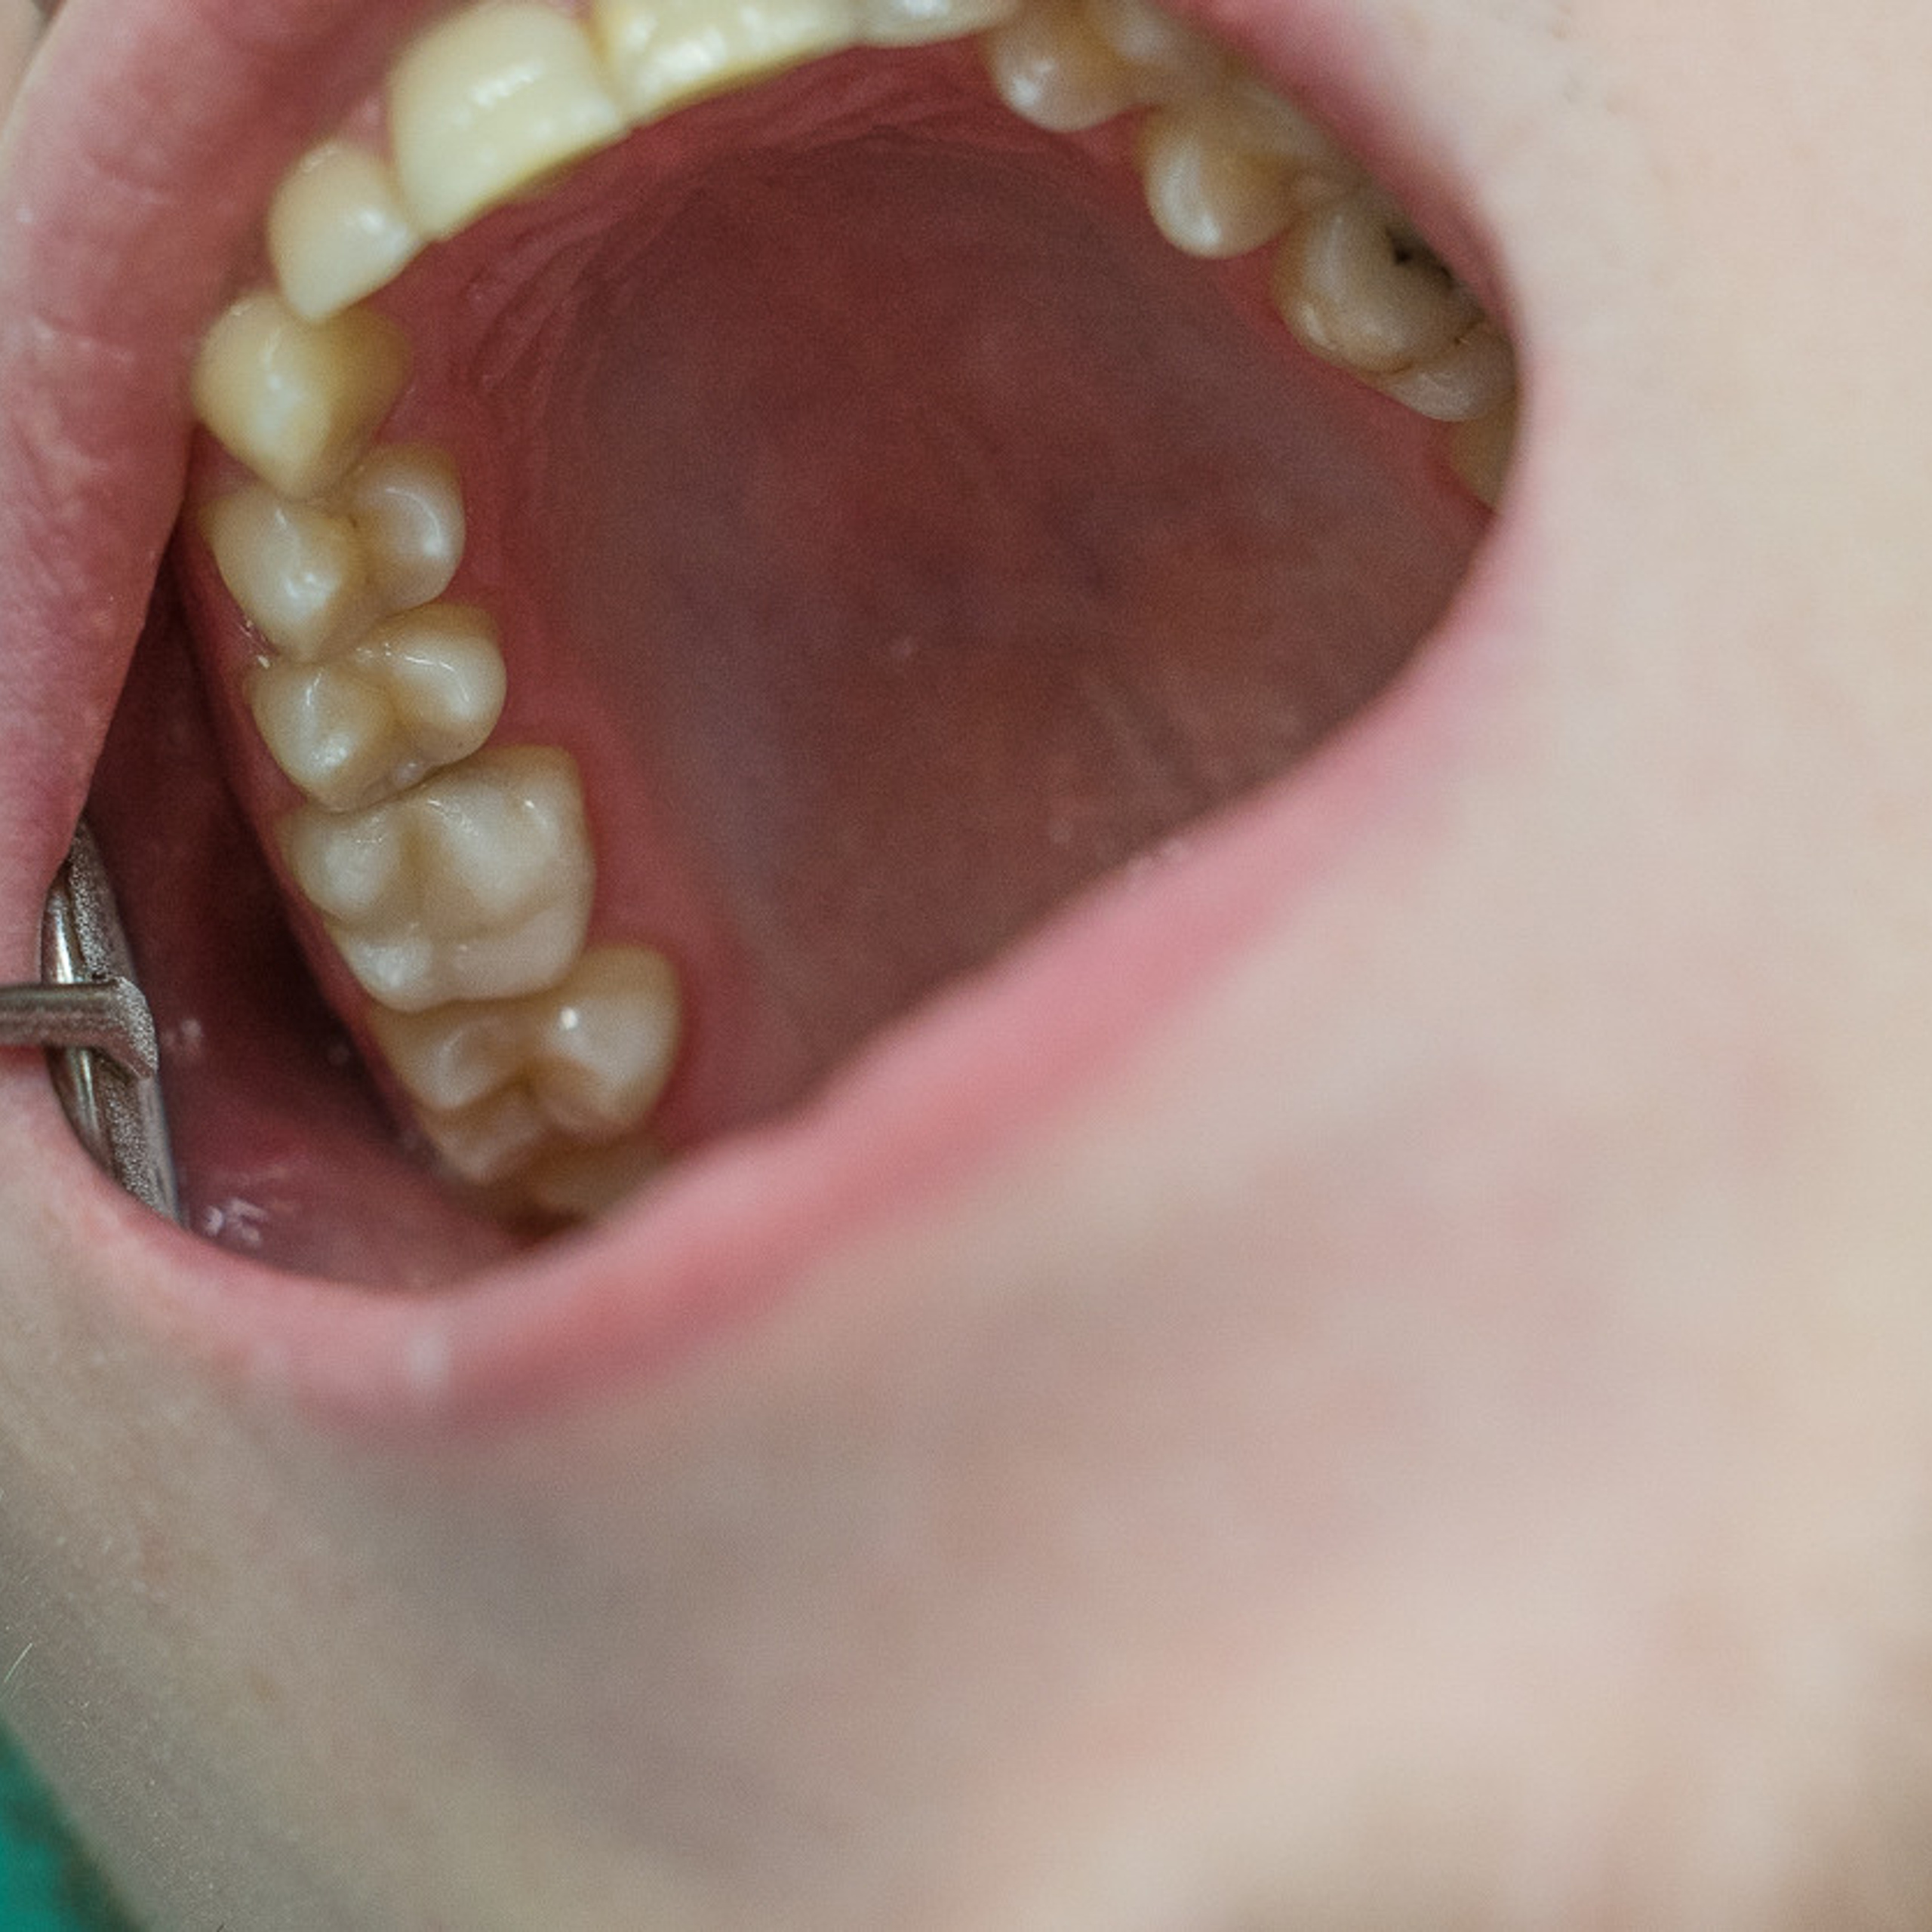

Фотографии учеников до обучения

Фотографии после обучения